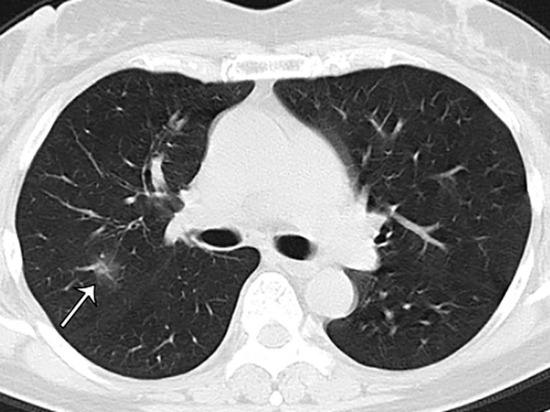

Коронавирустун белгилери байкалбаган бейтаптарда өпкөнүн жабыркашы аныкталды. Япониялык окумуштуулар Diamond Princess лайнериндеги 104 кишиден COVID-19 жуккан жүргүнчүлөрдүн абалын анализдешкен. Алар компьютердик томографиянын натыйжаларын изилдеп чыгышып, ушундай натыйжага келишкен. Бул тууралуу  МК.RU жазып чыкты.

Маалыматка ылайык, Diamond Princess кемесинин 104 жүргүнчүсүнүн ичинен 76 адамда (73%) коронавирус илдетинин белгилери байкалган эмес. Алардын ичинен 41 кишиден компьютердик томографиясынын жыйынтыгында илдетке чалдыккан адамдардын өпкөлөрүндө өзгөрүү бар экендиги белгилүү болгон.

Япон окумуштууларынын айтымында, коронавирустун белгилери адамда байкалбаса дагы илдетке чалдыккан бейтапка өз кесепетин  тийгизет.